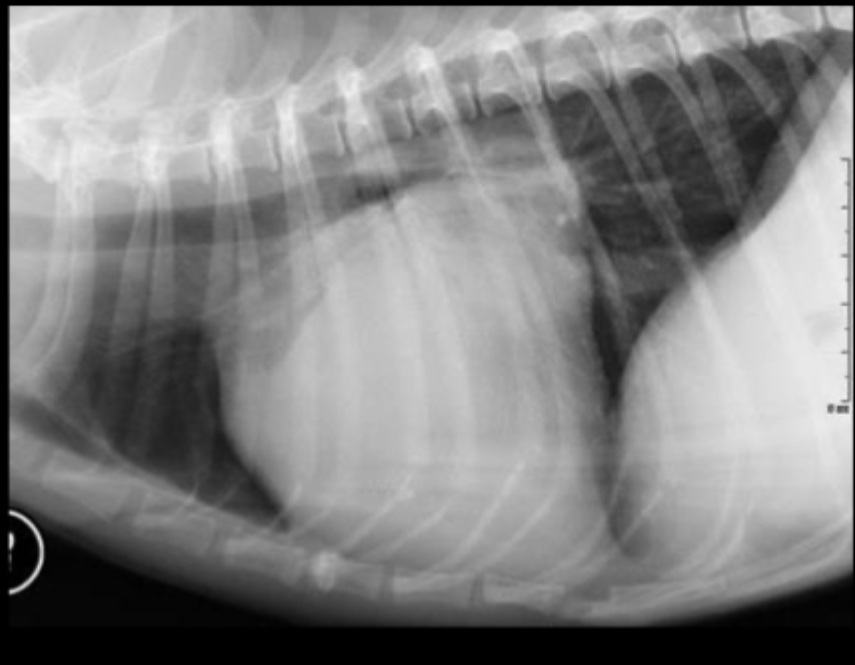

What part of the heart is enlarged in this lateral radiograph?

left atrium

What radiographic changes can we see on a lateral view if there is left atrial enlargement?

straightening of caudo-dorsal heart margin

What radiographic changes can we see on a VD view if there is left atrial enlargement?

splitting of mainstem bronchi

round opacity superimposed over caudal aspect of heart

with severe changes you can see left auricular appendage bulge at 2-3 o’clock on VD